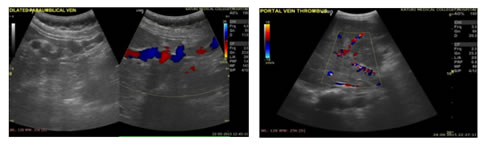

Figure 1:                                                                              Figure 2:

2

Figure 3:                                                                              Figure 4:

Figure 1: USG Axial image showing Dilated Portal Vein; Figure 2: USG Axial image showing Loss of Respiratory variations in Portal Vein diameter; Figure 3: Colour Doppler showing Flow reversal in Splenic vein; Figure 4: Colour Doppler Axial image: Flow reversal in SMV shown by arrow; Figure 5: USG Axial image showing dampened flow in Portal vein; Figure 6: HRUS image showing Nodular liver surface in cirrhosis

Figure 7: Spectral Doppler USG image: Showing Biphasic flow in Splenic vein; Figure 8: Gray scale and Colour Doppler USG image: Showing Cavernomatous transformation of Portal vein; Figure 9: Gray scale and Colour Doppler USG image; Figure 10: Showing Dilated Coronary vein with Hepatofugal flow; Figure 11: Gray scale and Colour Doppler USG image: Showing GEJ collaterals; Figure 12: Gray scale and Colour Doppler USG image: Showing Lienorenal collaterals; Figure 13: Gray scale and Colour Doppler USG image: Showing Recannalised Paraumbilical vein with hepatofugal flow; Figure 14: Colour Doppler USG image: Showing Absent Colour flow in Portal vein due to Thrombosis